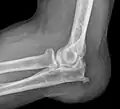

Bursitis (Synonym: Schleimbeutelentzündung; Plural: Bursitiden) ist die Entzündung eines Schleimbeutels (lateinisch Bursa synovialis). Sie entsteht durch Verletzungen, Infektionen oder durch Dauerreizungen, vor allem am Ellbogen, Kniegelenk und Schultergelenk. In der Veterinärmedizin wird die Symptomatik einer Bursitis auch als Stollbeule oder Galle bezeichnet.

Aufgrund ihrer oberflächlichen Lage direkt unter der Haut sind die drei Hautschleimbeutel des Kniegelenks (Bursa subcutanea praepatellaris, Bursa subcutanea infrapatellaris und Bursa subcutanea tuberositatis tibiae) und der des Ellenbogens (Bursa subcutanea olecrani) besonders durch Infektionen über kleinere Verletzungen sowie mechanische Reizung durch unphysiologische Belastungssituationen gefährdet. Meist kommt es durch mechanische Überbelastung (z. B. Knien - "housemaid knee", Sport, multiple Traumata) zu einer Reizung und infolgedessen zu einer Entzündung der Synovia. Diese Entzündung (früher auch als „Fibrositis“ der Schleimbeutel bezeichnet[1]) kann in selteneren Fällen auch durch eine chronische Entzündung (Rheuma, Gicht) oder eine systemische Infektion wie Tuberkulose bedingt sein.

Die Schleimbeutelentzündung des Ellenbogens (Bursitis olecrani) tritt bei exponierten Berufsgruppen wie Bergleuten häufiger auf. Der Umstand, dass auch die beim Lesen und Schreiben auf dem Tisch abgestützten Ellbogen häufiger von einer Entzündung betroffen sind, spiegelt sich in den scherzhaften Bezeichnungen Studentenellenbogen („student’s elbow“) sowie Bursitis informaticus olecrani.